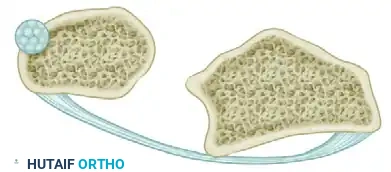

* A small tendon graft is harvested.

* The graft is looped circumferentially around the neck of the ulna to act as a neo-ligament.

Figure: An annular ligament is formed by looping the small tendon graft around the neck of the ulna and preparing it for attachment to the radius.